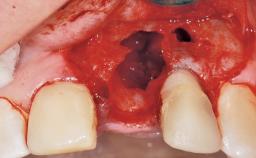

Placement Protocol Immediate implant placement

Socket Morphology Single-root socket

Socket Integrity Damage to one or more bone walls

Bone Volume Damage to one or more socket walls